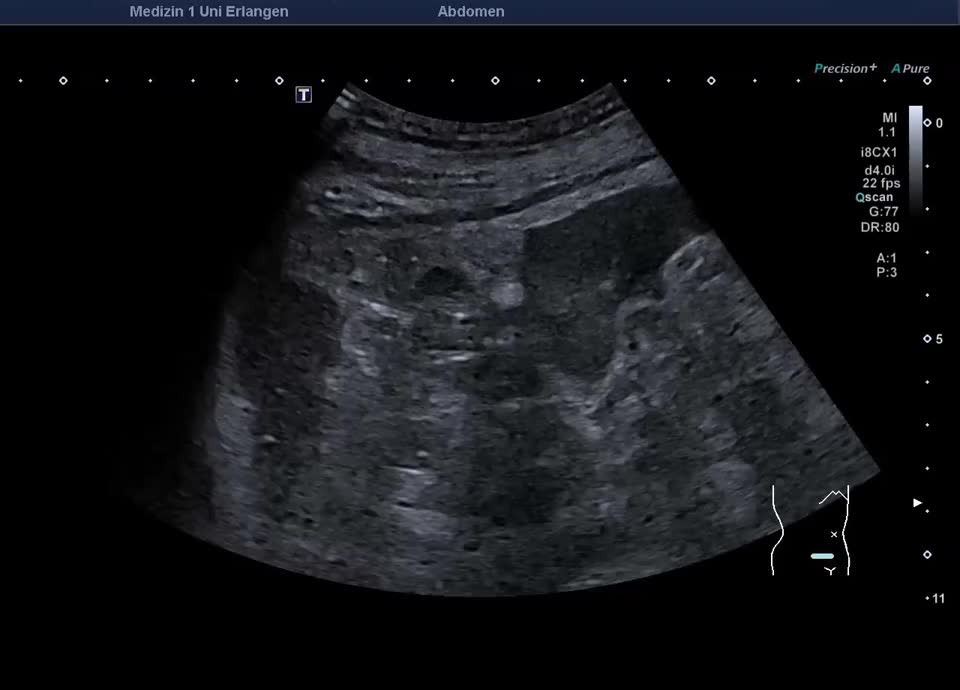

• Subcutaneous metastasis (color Doppler, video)

• Subcutaneous metastasis (color Doppler)

• Psoas metastasis of urothelial carcinoma (color Doppler)